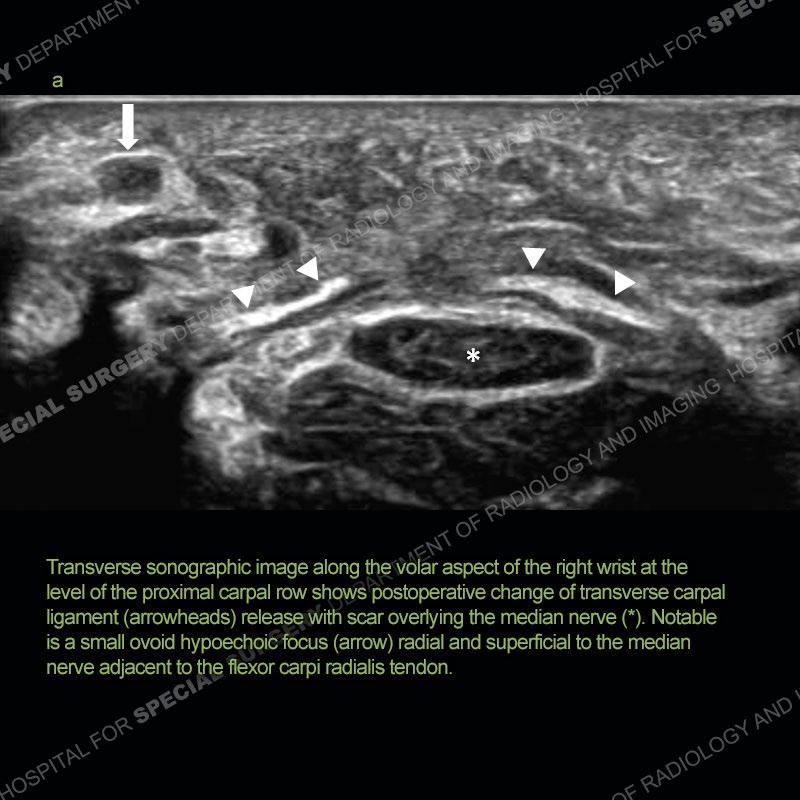

63 year old female 3 months status post right carpal tunnel surgery with 1 week of increased right wrist volar-sided pain.

Neuroma of the Palmar Cutaneous Branch of the Median

Nerve Following Carpal Tunnel Surgery

The palmar cutaneous branch of the median nerve provides sensation to the proximal palmar skin particularly over the thenar eminence.

This nerve is vulnerable to injury during surgery along the volar aspect of the wrist, most commonly seen with carpal tunnel release.

Injury to this nerve may manifest as a period of proximal palmar numbness after surgery followed by increased pain from neuroma formation.